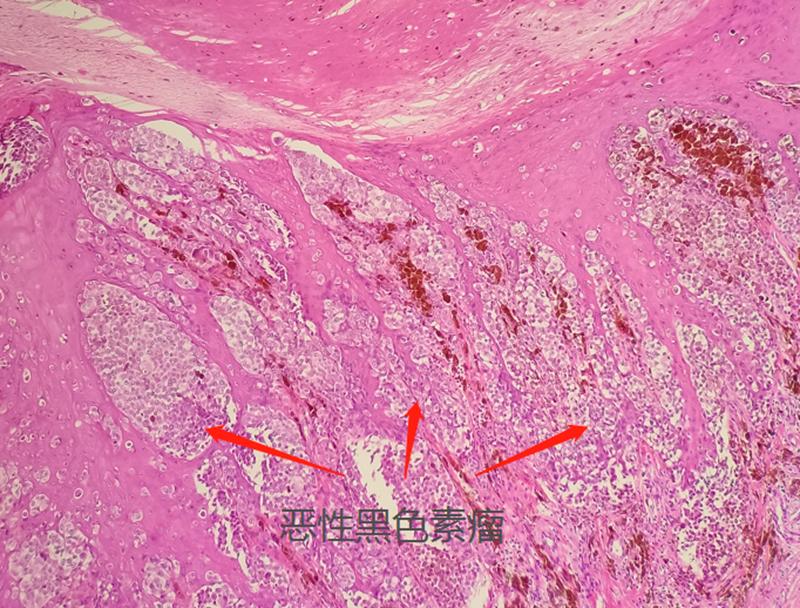

顾栋桦表示,黑色素瘤作为一种发病率很低的恶性肿瘤,本身也没有必要过于恐慌。大部分的痣都位于皮肤,易于观察,能够早期被发现。一旦出现异常状况,一定要咨询医生,并做相应的检查。确诊黑色素瘤的唯一办法是切除病变组织并做病理学诊断,医生会把疑似黑色素瘤部位的皮肤组织全部或部分切除,随后组织会被送到病理科进行病理学诊断。